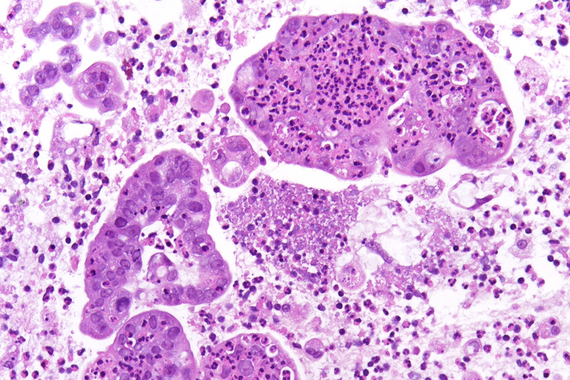

Ultrasound-guided biopsy of a pancreatic lesion in a 38-yeard-old woman (histological and cytological correlation).